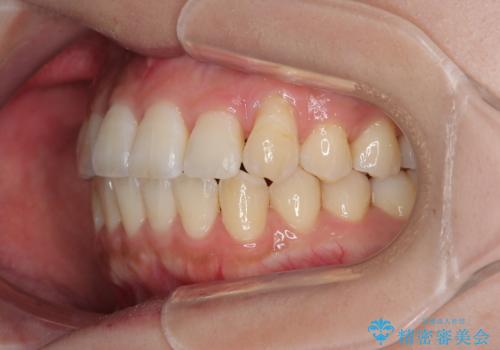

上顎の拡大は、左右どちらに拡大していくのか予想が困難ですが、こちらの患者様では結果として上下正中が一致する方向に拡大され、非常にきれいな仕上がりとなりました。